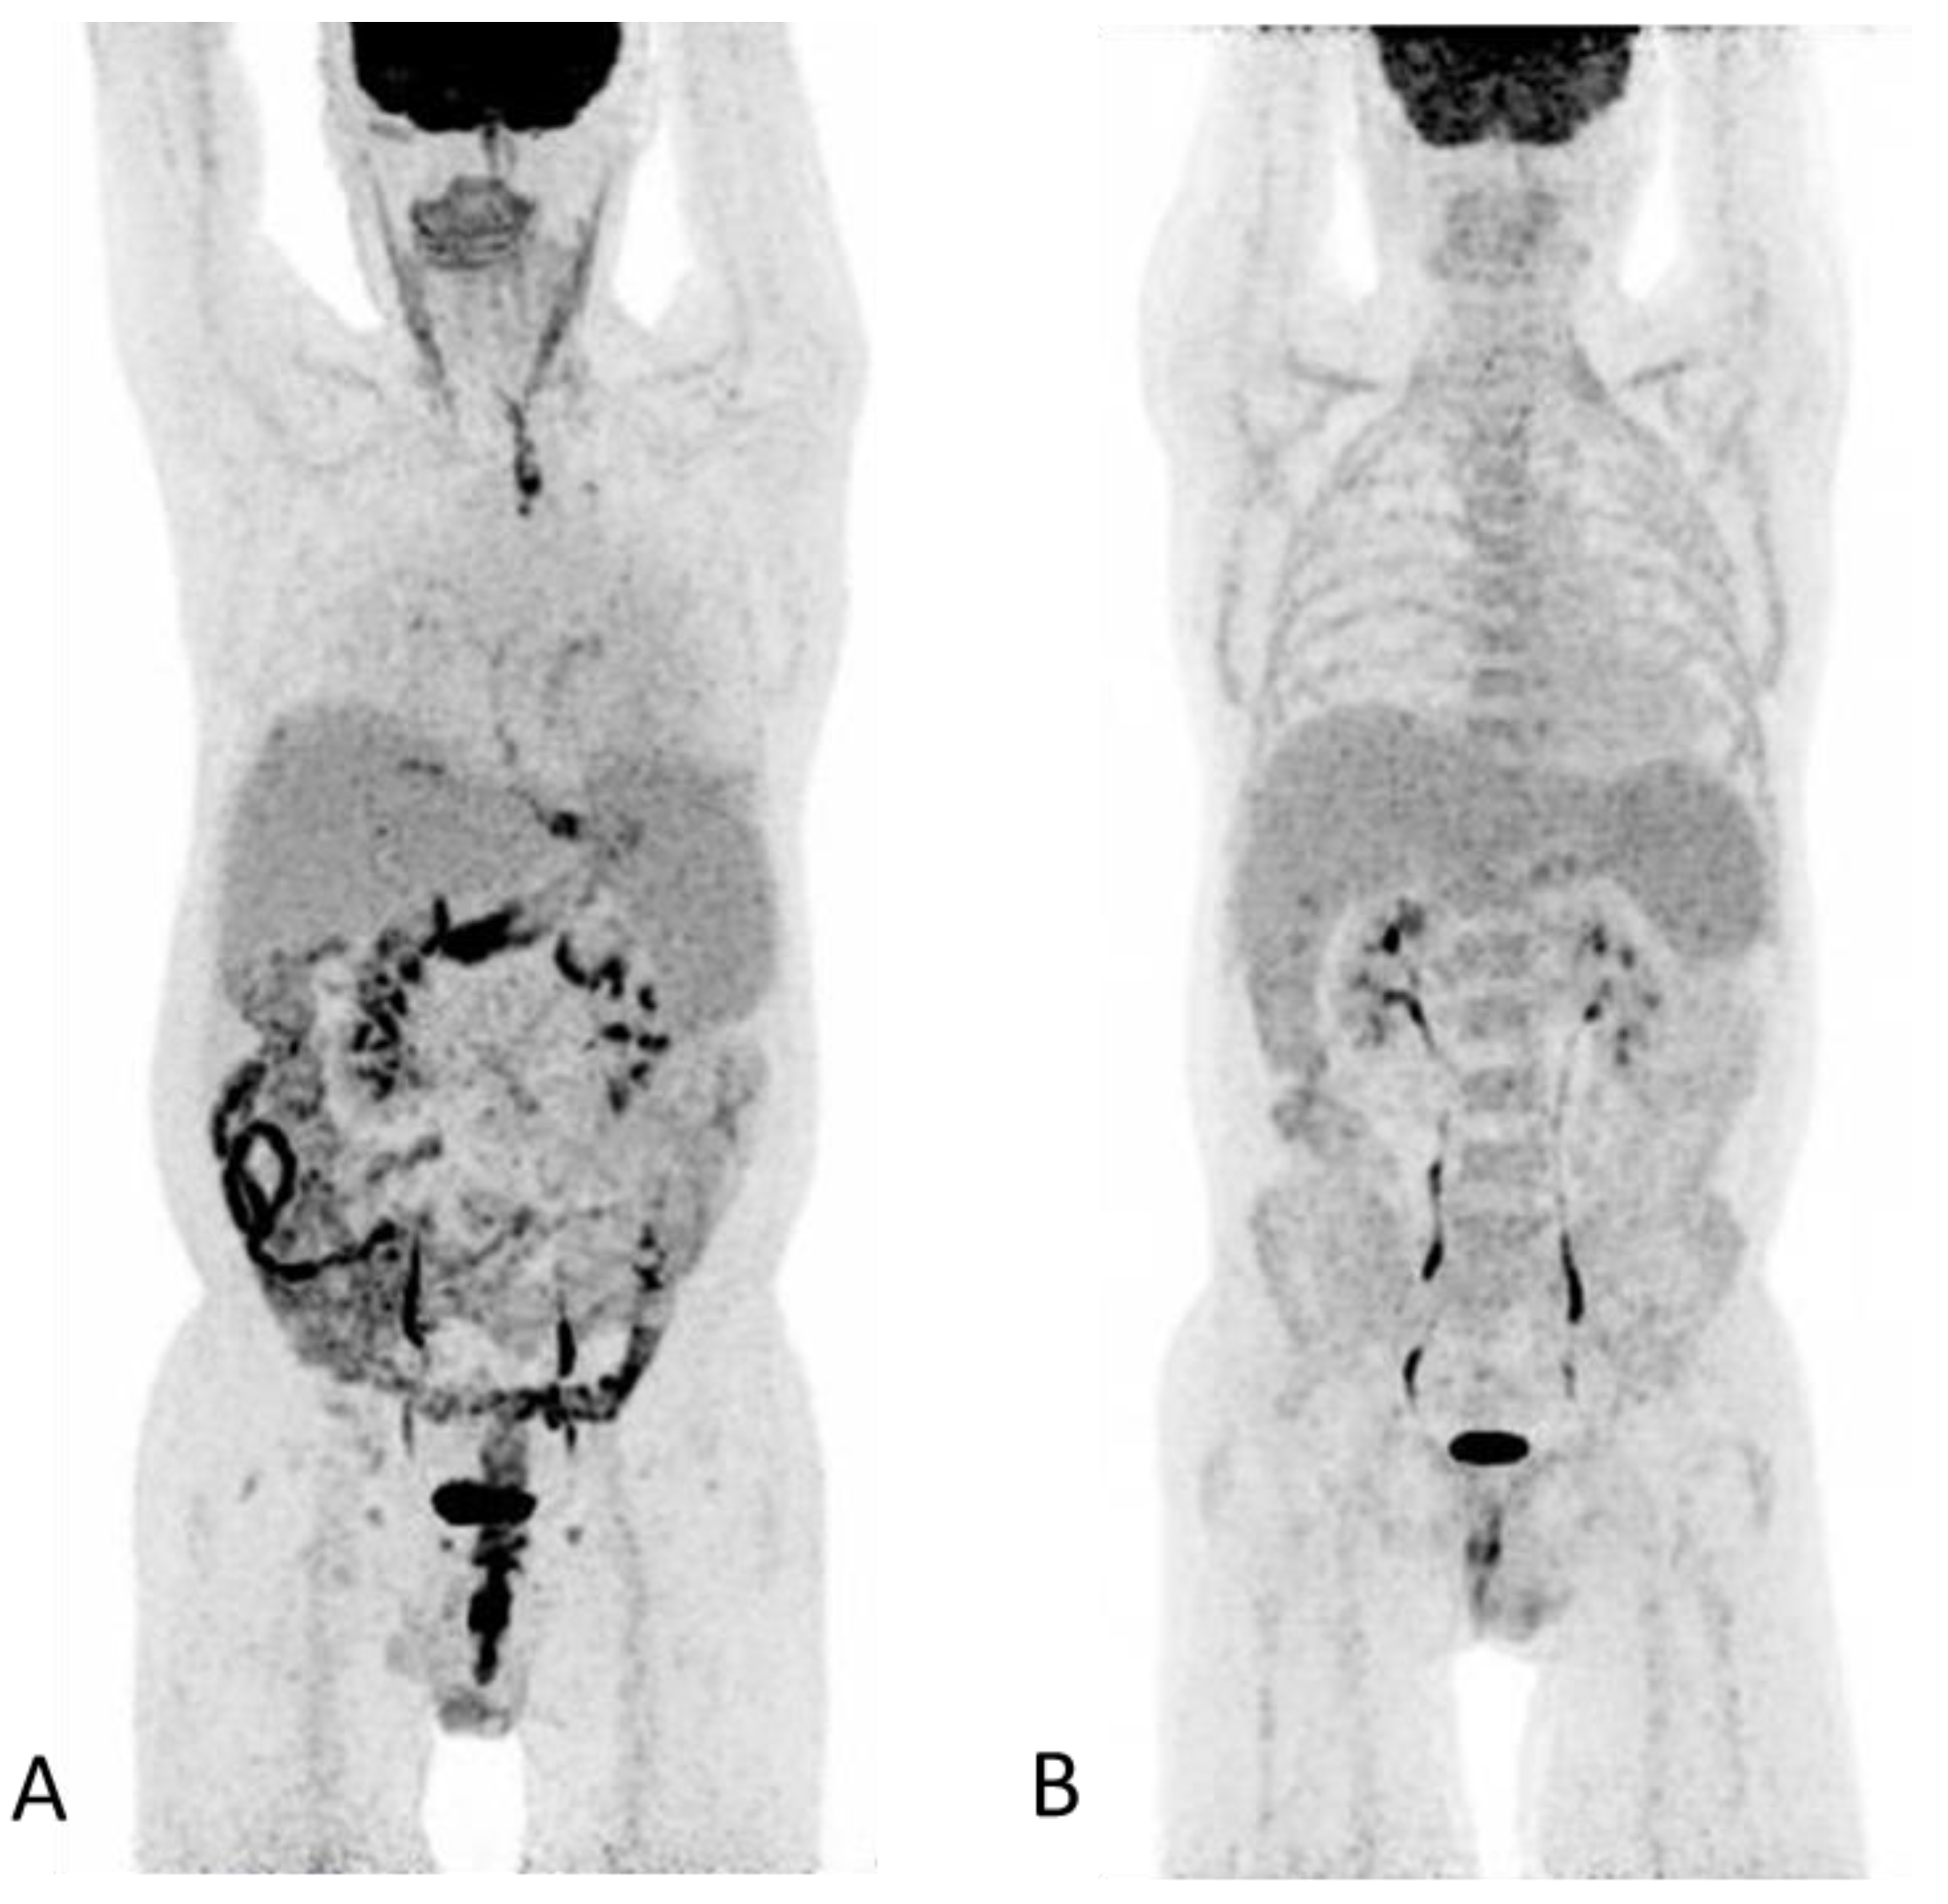

(A) An 18F-FDG PET/CT, with intravenous and oral contrast enhancement, was performed in a 50-year-old man 93 days post autologous SCT for relapse of Hodgkin’s lymphoma. The PET maximum intensity projection (MIP) image shows discontinuous pathological FDG-uptake throughout the GIT extending from the upper esophagus to the anal canal involving the cardia region, ventricle, and segments of the small-and large bowel including the rectum. The PET findings are consistent with an inflammatory response with normal physiological FDG-uptake in unaffected segments of the GIT. At the time of scanning, the patient had severe diarrhea, fever, nausea and reported weight loss but no skin lesions. The clinical presentation with non-specific symptoms and and that the patient was a recipient of autologous SCT rendered infection as a probable diagnosis. However, repeated blood and stools tests for bacterial, common viral and fungal agents were negative. Diagnosis was based on rectal biopsies that showed epithelial cell apoptosis indicative of GVHD according to previously described criteria [1]. No infectious agents were present. Despite intensive treatment the patient succumbed due to complications following sepsis. (B) Normal 18F-FDG PET/CT in the same patient performed immediately post-autologous SCT. Amid the two scans it is evident that the spleen has increased in size resulting in splenomegaly (A). Splenomegaly has previously been described as an extra intestinal finding in acute GVHD-GIT [2]. Clinically, GVHD is divided into acute or chronic GVDH with acute GVHD developing within the first 100 days post-SCT and chronic GVHD as occurring beyond the first 3 months [3]. GVHD is a leading cause of morbidity and mortality in recipients of allogenic SCT. Auto-GVHD has the same clinical and histological presentation as allo-GVHD but is often observed as milder, self-limited and less frequent [4,5,6]. The standard treatment of acute GVHD is steroids, however, acute auto-GVHD can often resolve without treatment, although, fatal cases have been reported [4,5,6,7]. The primary affected organs are the skin, liver and GIT [8], if all three organs are involved diagnosis could be made on clinical grounds alone. Isolated GVHD-GIT is much more challenging to diagnose due its often non-specific symptoms such as abdominal cramping, nausea and vomiting, voluminous and often bloody diarrhea and fever that in the setting of post-HSCT could be treatment related or infectious. 18F-FDG PET/CT has been proposed as a non-invasive imaging modality in assessing intestinal GVHD, map its localization and monitor treatment response [9,10,11]. Here, we present an 18F-FDG PET/CT scan where many of the most common reported CT and PET/CT features of GIT-GVHD were present [2,9]. Common PET/CT features of bowel inflammation are non-specific and could represent inflammatory bowel disease such as enterocolitis, Mb Crohn or ulcerative colitis the discontinuous pattern and extent (from esophagus to rectum) of GIT involvement led to us to suggest GVHD as a differential diagnosis. However, caution must be taken for false positive results with/or without accompanied morphological changes. A previous study reported false-positive results for acute-GVHD related to daily metformin treatment [10]. Other pathological underlying causes for pathological FDG-uptake in the GIT must be considered, such as malignancy, benign neoplasms or inflammation due to esophagitis or gastritis [12]. Furthermore, physiological FDG-uptake within the normal GIT is highly variable and findings should be interpreted with care [12]. In this case, many of the possible differential diagnosis could be excluded due to a recently previous FDG-PET/CT scan (B) available for comparison which rendered a new malignancy as improbable and the patient had no medical history of inflammatory bowel disease or metformin treated diabetes.